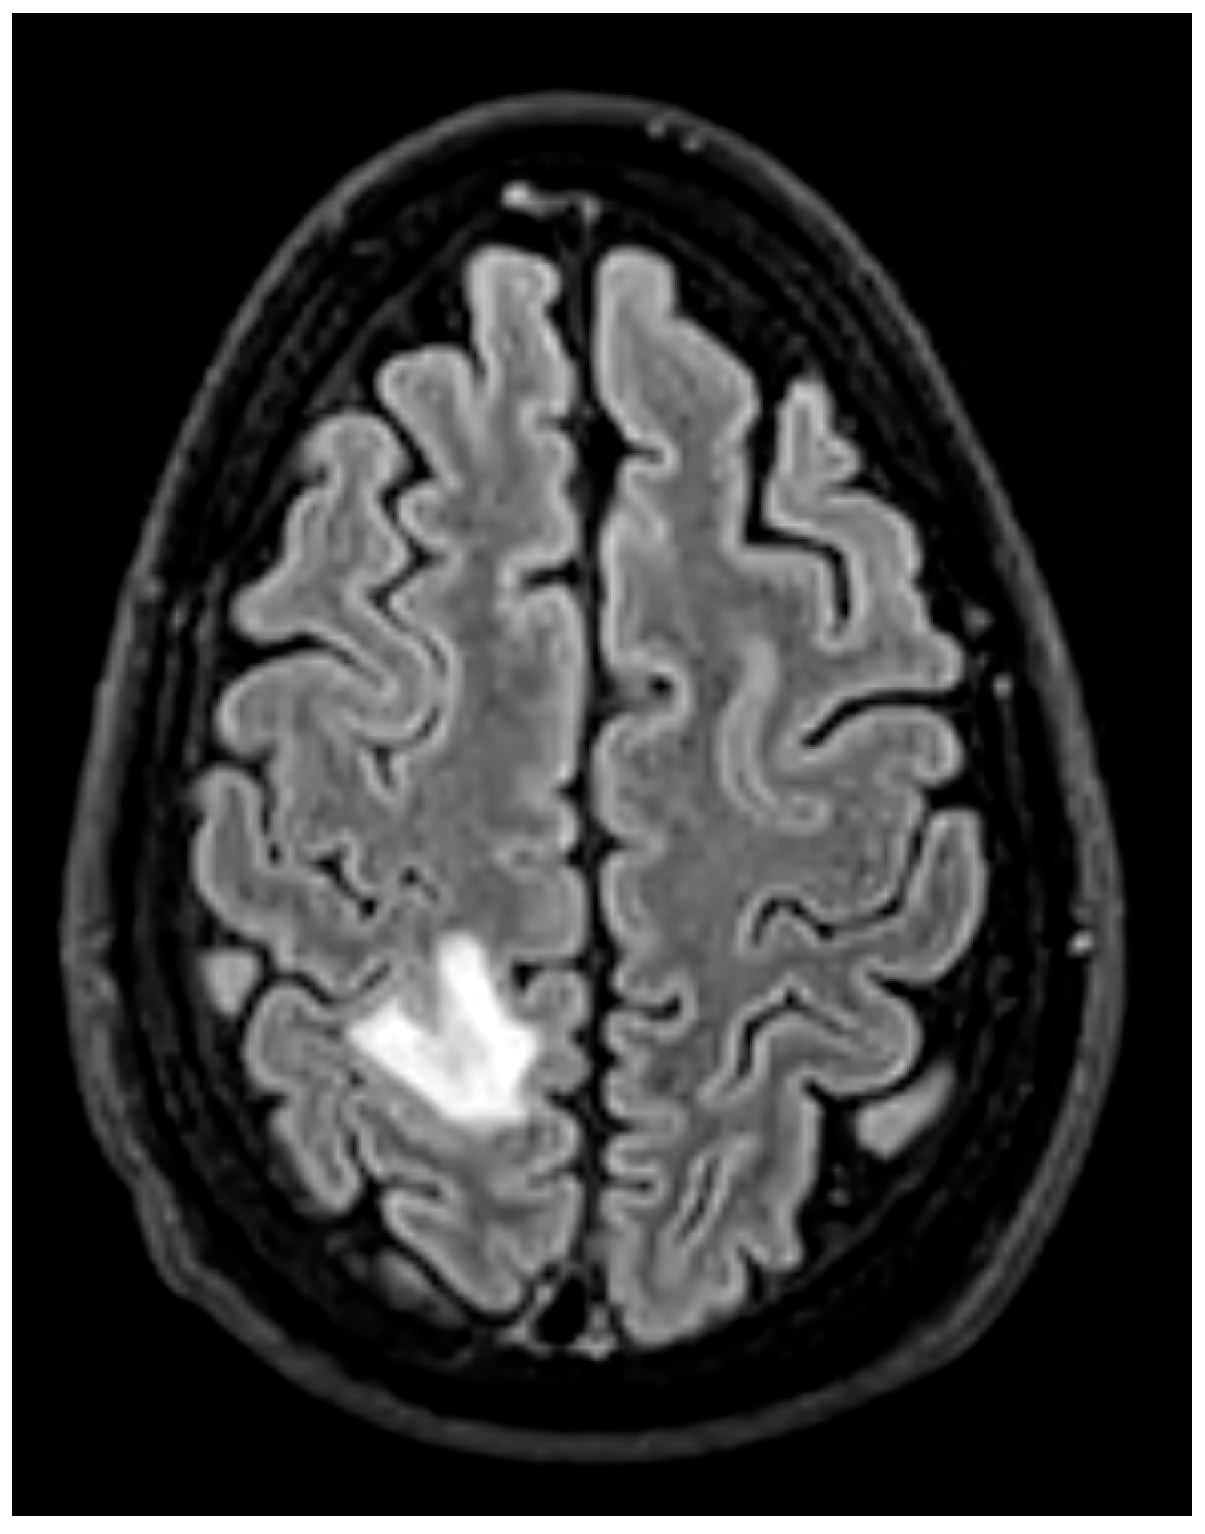

- Brain MRI is especially valuable for identifying clinically occult cerebral emboli, which can influence management decisions and prognosis [24,36] (Figure 15). These occur in 20–40% of IE cases, and a significant portion are clinically silent. Brain MRI with diffusion-weighted imaging (DWI) is the most sensitive modality for detecting acute cerebral infarcts, microabscesses, mycotic aneurysms, and hemorrhages [35,38]. Identifying these findings, even in asymptomatic patients, is critical as it can significantly influence surgical timing and risk stratification. The 2023 ESC guidelines recommend considering brain MRI before cardiac surgery in patients with IE, especially in those with neurological symptoms or high-risk clinical features [13]. For example, the presence of a large cerebral infarct, hemorrhagic lesions, or mycotic aneurysms may prompt delay of valve surgery to reduce the risk of perioperative neurological complications. Conversely, detection of small, non-hemorrhagic embolic lesions may support earlier surgery to prevent further embolization [30]. Prospective data demonstrate that routine cerebral MRI led to changes in surgical plans in up to 14% of cases, including both delays and accelerations of surgery based on neurological risk [39].

- vs. FDG-PET/CT: PET/CT excels at detecting metabolic activity, making it superior for diagnosing active infection around prosthetic material and identifying occult septic emboli throughout the body. MRI does not assess metabolism but provides exquisite anatomical detail of embolic lesions (e.g., defining the exact size and hemorrhagic component of a splenic infarct) and can detect complications like cerebral microabscesses with higher sensitivity than CT [17,18].

- Search for Silent Emboli: A single clinically apparent embolus is often the “tip of the iceberg.” The discovery of one embolic event mandates a systematic search for other, silent emboli, particularly cerebral, which can drastically alter surgical risk and timing. As such, whole-body CT angiography or FDG-PET/CT is recommended to define the full embolic burden [13,39]. Brain MRI is the gold standard for detecting silent cerebral emboli and should be strongly considered before surgery in high-risk patients, even in the absence of neurological symptoms [22].

- Impact of Silent Emboli: The discovery of multiple silent emboli, particularly cerebral, creates a complex risk-benefit calculus. While not a direct surgical indication, it necessitates a nuanced, multidisciplinary decision regarding the timing of surgery to balance the risk of recurrent embolism against the risk of hemorrhagic transformation of cerebral infarcts.

- Advanced Modalities Offer Complementary Data: Cardiac CT excels at defining paravalvular anatomy for surgery, FDG-PET/CT detects occult metabolic activity and emboli, and MRI is indispensable for diagnosing silent cerebral complications.